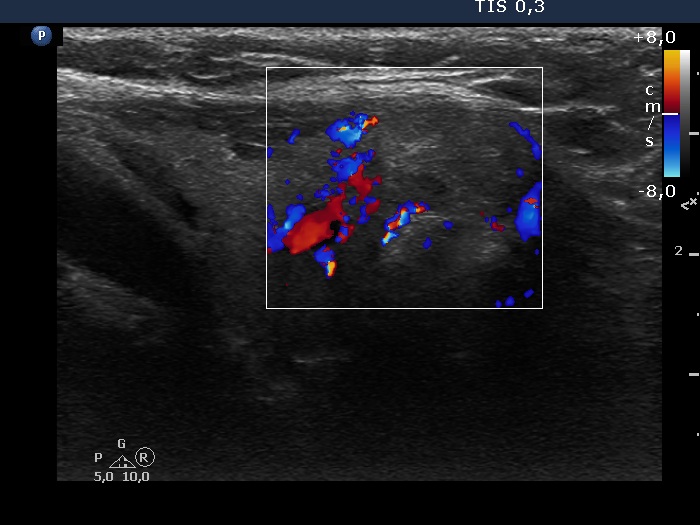

Right lobe, longitudinal scan

Isthmus, longitudinal scan, color Doppler mode. Ther nodule is avascular.